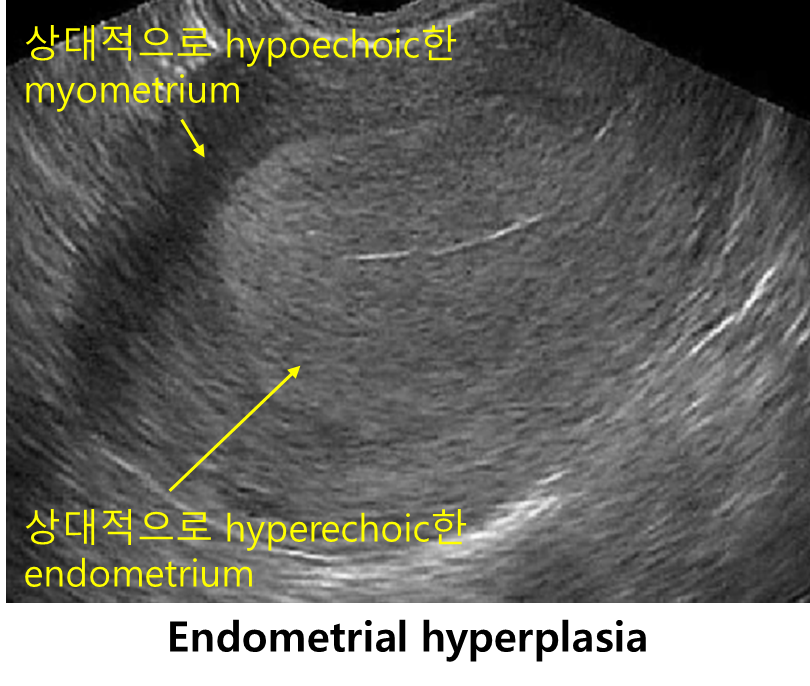

: Endometrial hyperplasia

2) US: 자궁내막 두께 측정

(1) 폐경 전: > 14 mm (정상 기준치가 명확하지 않음)

(2) 폐경 후: > 4 mm